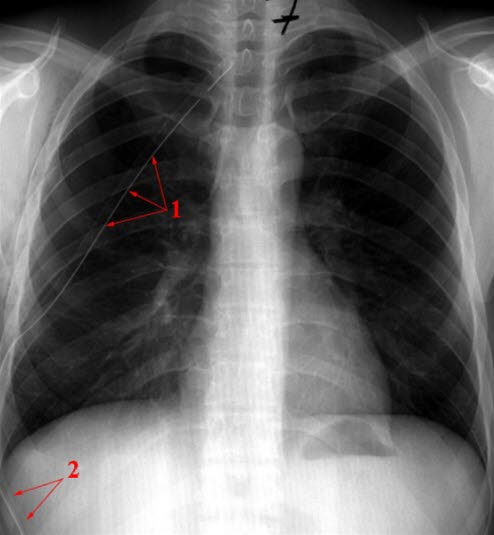

Ventilpneumothorax - behandlet

Korrigering av pneumothorax med innlagt dren (1 og 2)